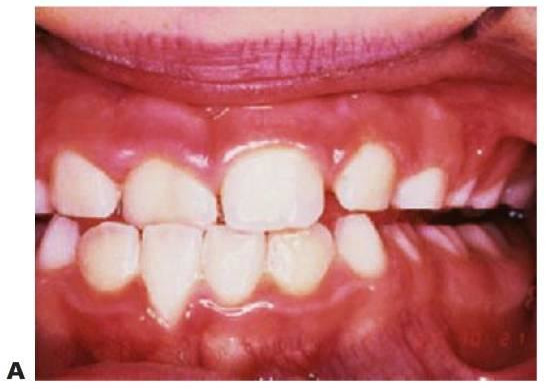

Hasta un 10% de los niños presentan mordida cruzada, pudiéndose presentar tres tipos diferentes de mordida cruzada anterior en la fase de dentición mixta.

Incisivos ectópicos

Un incisivo puede erupcionar de forma ectópica en palatino del maxilar o en labial de la mandíbula hacia una relación de mordida cruzada en oclusión céntrica. Este hecho puede suceder en un niño con una relación esquelética equilibrada y tan sólo se precisa un trata miento temprano en el caso de manifestarse una desviación en la apertura y/o cierre, en el caso de oclusión traumática o bien en el caso de existir una preocupación periodontal. De otra manera, el tratamiento puede retrasarse hasta que toda la dentición permanente erupcione.

Maloclusión esquelética de clase III

Una mordida cruzada anterior puede relacionarse con una discrepancia esquelética de clase III de modo que los incisivos se encuentran en un resalte negativo al cerrar en oclusión céntrica sin desviación del cierre mandibular, aunque estén colocados de forma correcta dentro de los rebordes alveolares.

Maloclusión de seudoclase III

Este patrón se presenta donde exista un patrón habitual de cierre mandibular que muestra a la mandíbula entrando en una mordida protrusiva, de manera que la mordida cruzada de los incisivos evita la oclusión traumática con la posición lingual de uno o varios incisivos maxilares. Así, el desplazamiento anterior de la mandíbula puede afectar al crecimiento tanto del maxilar como de la mandíbula y acompañarse de una adaptación muscular inadecuada.